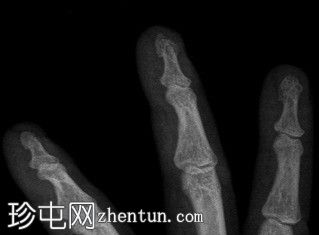

右手X光片显示中指远端指骨末端失去正常的光滑轮廓,皮质轮廓不规则,提示远端骨折畸形。骨折在斜位片上更容易被看到,并伴有轻度移位和周围软组织肿胀。

X光片结果显示中指远端指骨末端骨折,皮质轮廓不规则,正常轮廓丧失,可能由直接创伤引起,例如重物撞击或挤压伤。